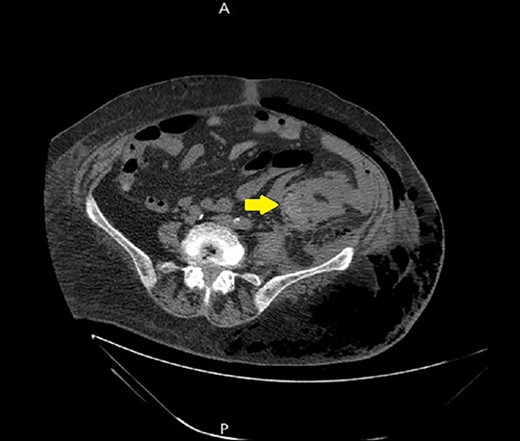

Ultrasound showed extensive subcutaneous soft tissue edema with hyperechoic areas seen in the proximal anterolateral part of the thigh. The initial diagnosis of the condition was a left iliopsoas abscess. Due to the severity of the patient’s symptoms, a non-contrast abdomen and pelvis computerized tomography (CT) scan was done (Fig. 3), which showed a large amount of subcutaneous emphysema within the left flank soft tissues that wrapped anteriorly along the left lower lateral abdominal wall with a small tract of air extending from the left retroperitoneum posterior to the left kidney and extending along the left iliopsoas muscle inferiorly. A skin defect with the underlying abscess collection and air–fluid level was noted (Fig. 4). Another CT scan section saw a soft tissue mass lesion at the distal descending colon (Fig. 5). The abscess drainage was done under CT guidance.

A non-contrast abdomen and pelvis CT scan, which shows a skin defect with underlying abscess collection and air–fluid level, with significant subcutaneous air collection.